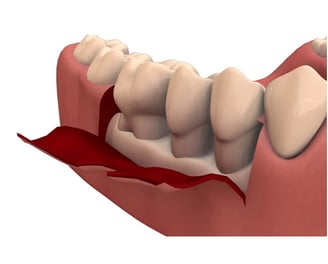

Es un procedimiento quirúrgico donde se levantan las encías para acceder a las raíces de los dientes y limpiar áreas profundas. Luego se reubican y se cosen las encías en su lugar para promover una mejor cicatrización.

Cirugía de Colgajo